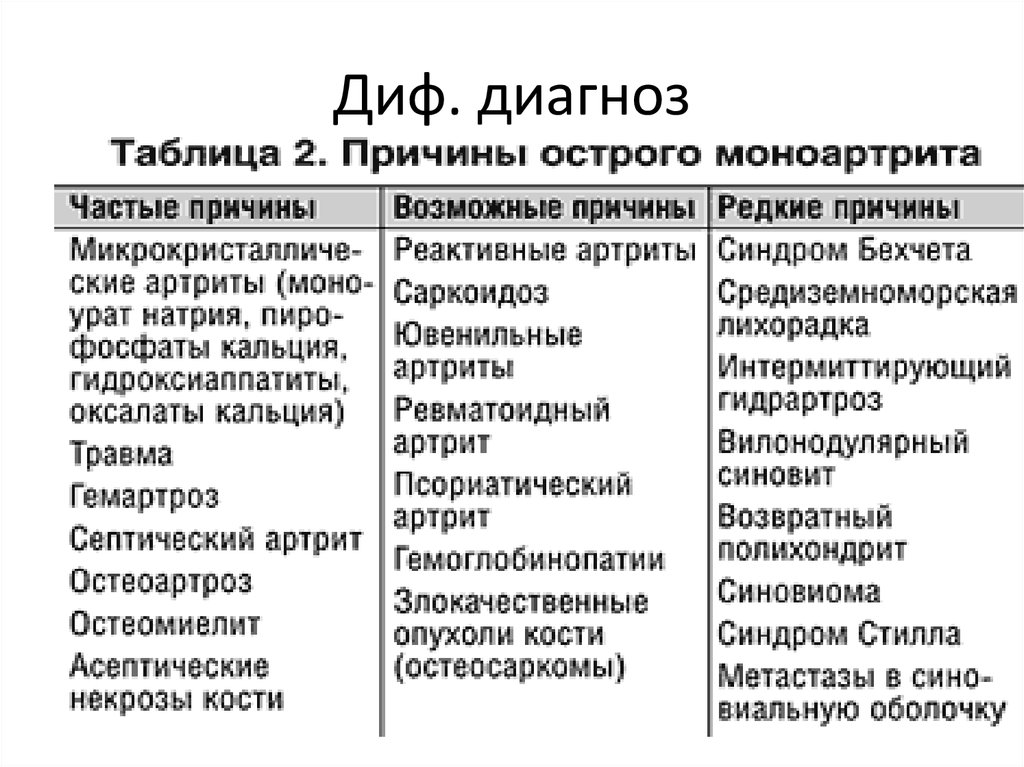

Дифференциальная диагностика заболеваний плевры